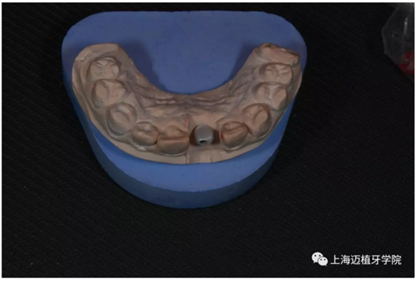

轉(zhuǎn)移模型

取工作模型

非工作模型

氧化鋯個(gè)性基臺